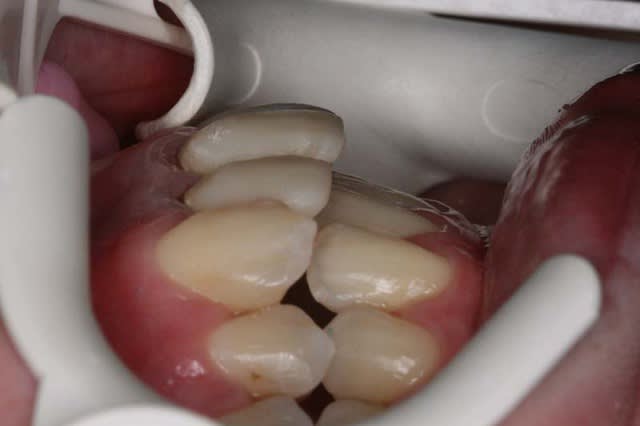

Le jeune confrère lui a dit avoir réalisé les provisoires de 12/11 en supra-gingival pour laisser la gencive redescendre, mais il n’a pas rectifié le surbombé des dents provisoires du commerce

ce que j’ai fait, on verra bien à la prochaine consultation